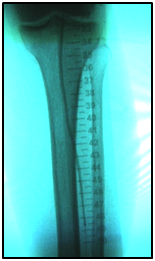

An example: A 77-year-old, diabetic woman, complaining of rest pain in her left leg and carrier ulceration on the left hallux. The physical examination showed absence of distal pulses in her left leg. Color Doppler ultrasound performed before treatment confirmed BTK critical lesions with no patency and a diagnosis of CLI.

Endovascular procedure was done with antegrade access in the ipsilateral common femoral artery, diagnostic angiography confirmed: Patency of the femoral-popliteal axis, occlusion of the posterior and anterior tibial arteries, two critical stenotic lesions in the fibular artery and revascularization of the dorsalis pedis and plantar arteries by the fibular artery. To treat the fibular critical atherosclerotic lesions were performed a percutaneous transluminal angioplasty using a 0.0018in.guidewire, catheter support and a catheter balloon (3,0x6 mm and 3,5x 15mm).